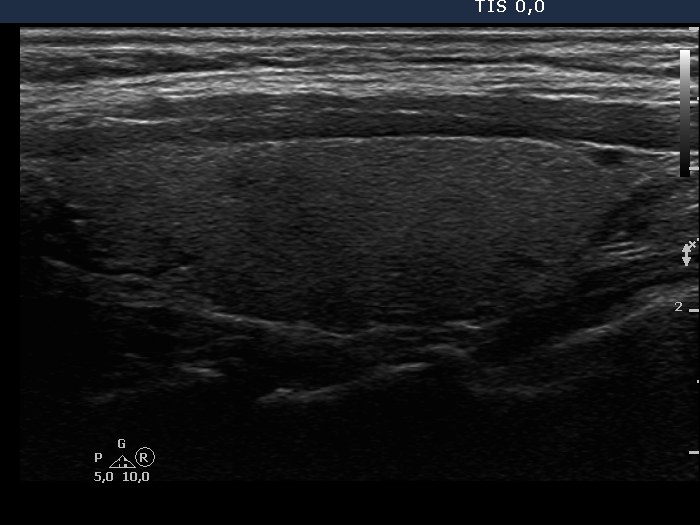

Ultrasonography: the thyroids were intact, i.e. the basic echo structure was echonormal and only a few small hypoechogenic areas were found. The echogenicity index was less than 1%. The vascularization was not specific.